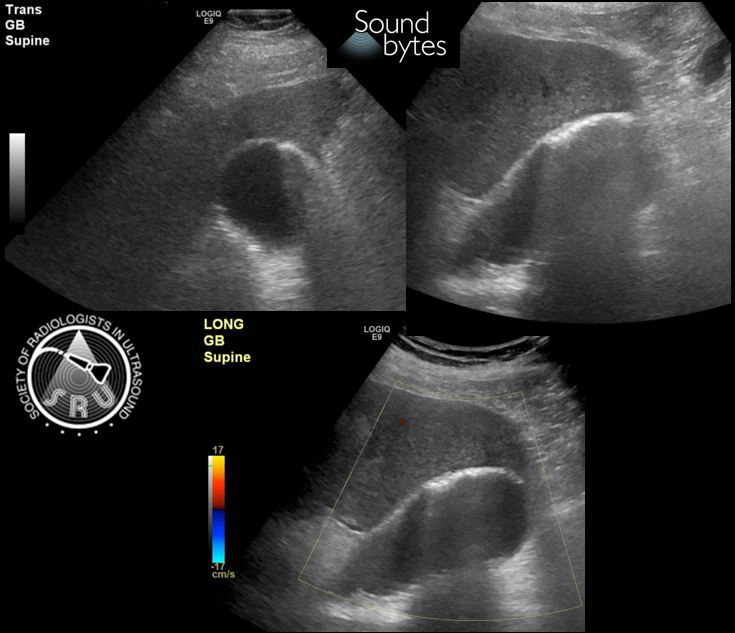

Last FM intern POCUS session of the academic year. Textbook gallbladder with duodenum shot - done at first try! 💪🏼 (flipped because selfie). Proud mama 🧸

@sruradiology

Answer to last week's case: Emphysematous Cholecystitis. Thanks for playing. Note the non dependent echogenic foci in the wall with “dirty” posterior shadowing. Has a high risk for perforation and high mortality rate. #Ultrasound #RadRes